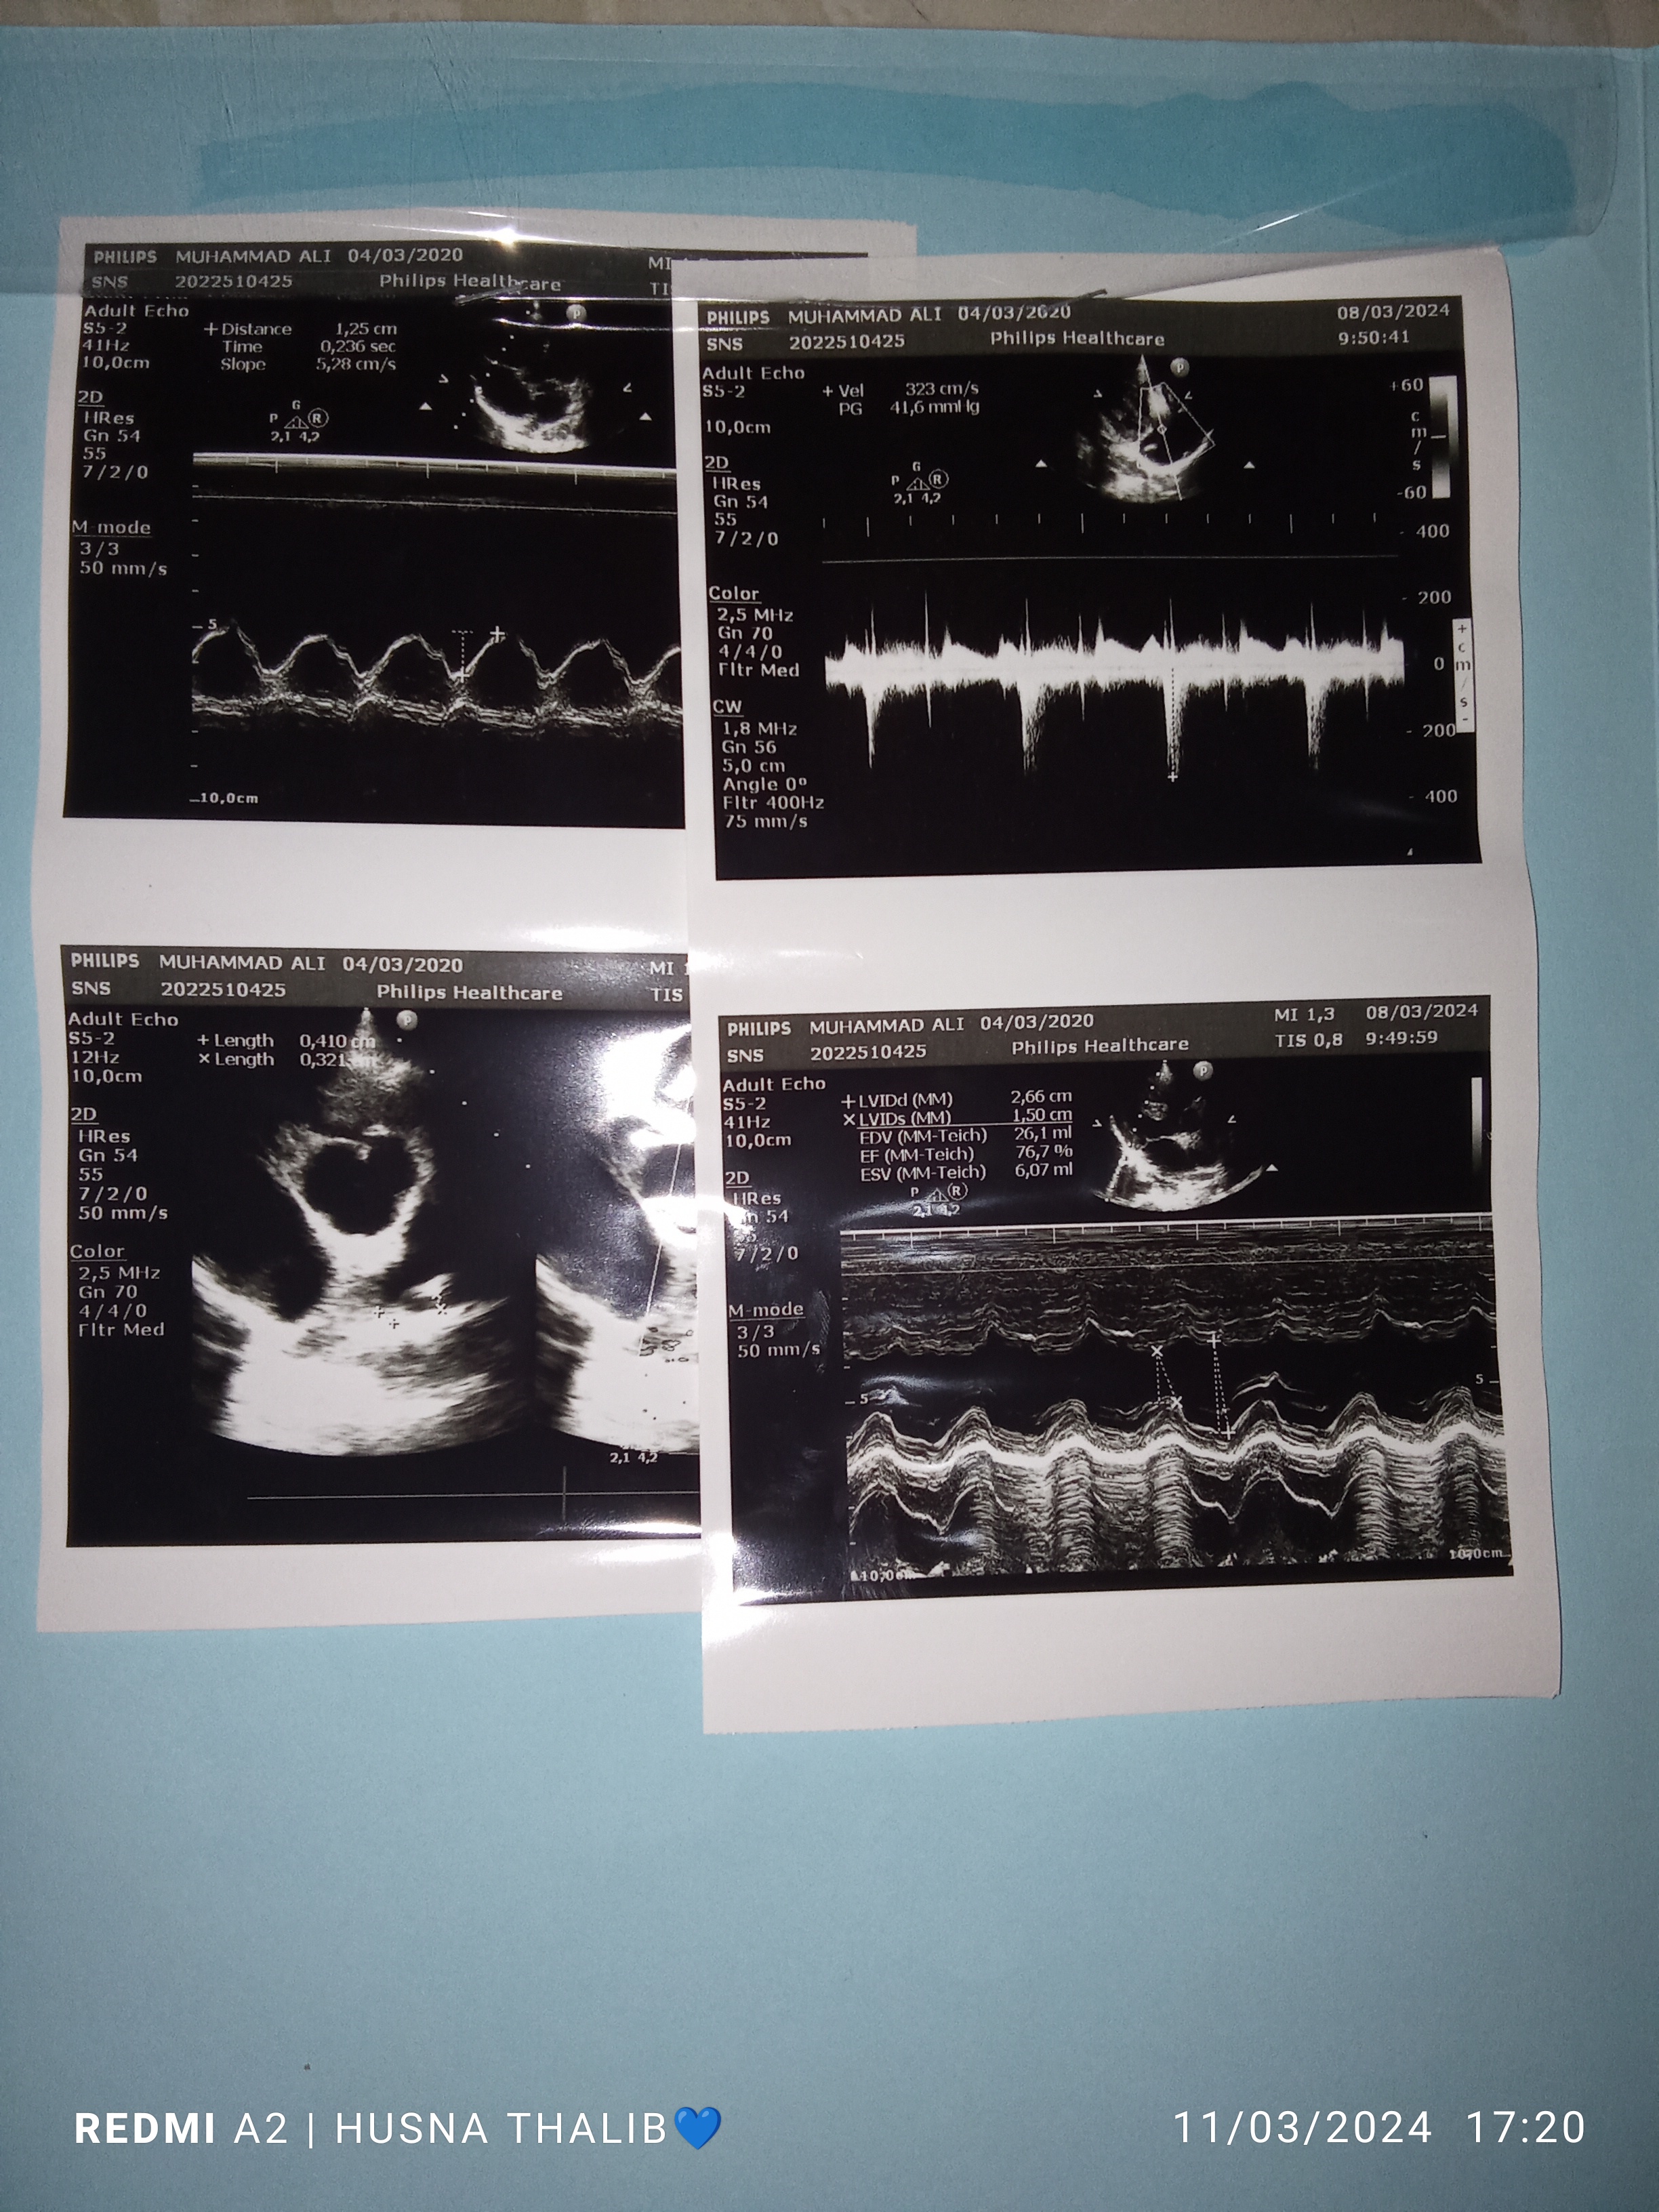

Aku hanya ingin mengabarkan mengenai kondisi “Ali Hamzah” anakku saat ini. Alhamdulillah anakku sehat dan sedang melengkapi beberapa berkas pemeriksaan di Rumah Sakit Daerah seperti echo terbaru dan rontgen terbaru secara rutin setiap Rabu, Kamis dan Jumat sesuai arahan dokter. Doakan anakku ya TemanBaik agar ia sehat selalu dan semoga ada kabar baik untuk hasil rapat bedanya.